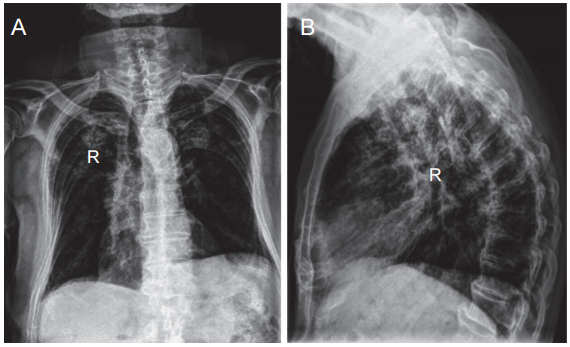

辅助检查:血常规、凝血功能、感染四项等化验结果均未见明显异常,尿常规:葡萄糖 (±),镁离子:0.76 mmol/L,血糖:8.16 mmol/L。完善胸椎 X 线片(见图2)、胸椎磁共振检查(见图3)。

图2 胸椎 X 线片

(A) 胸椎 X 线片正位;(B) 胸椎 X 线片侧位